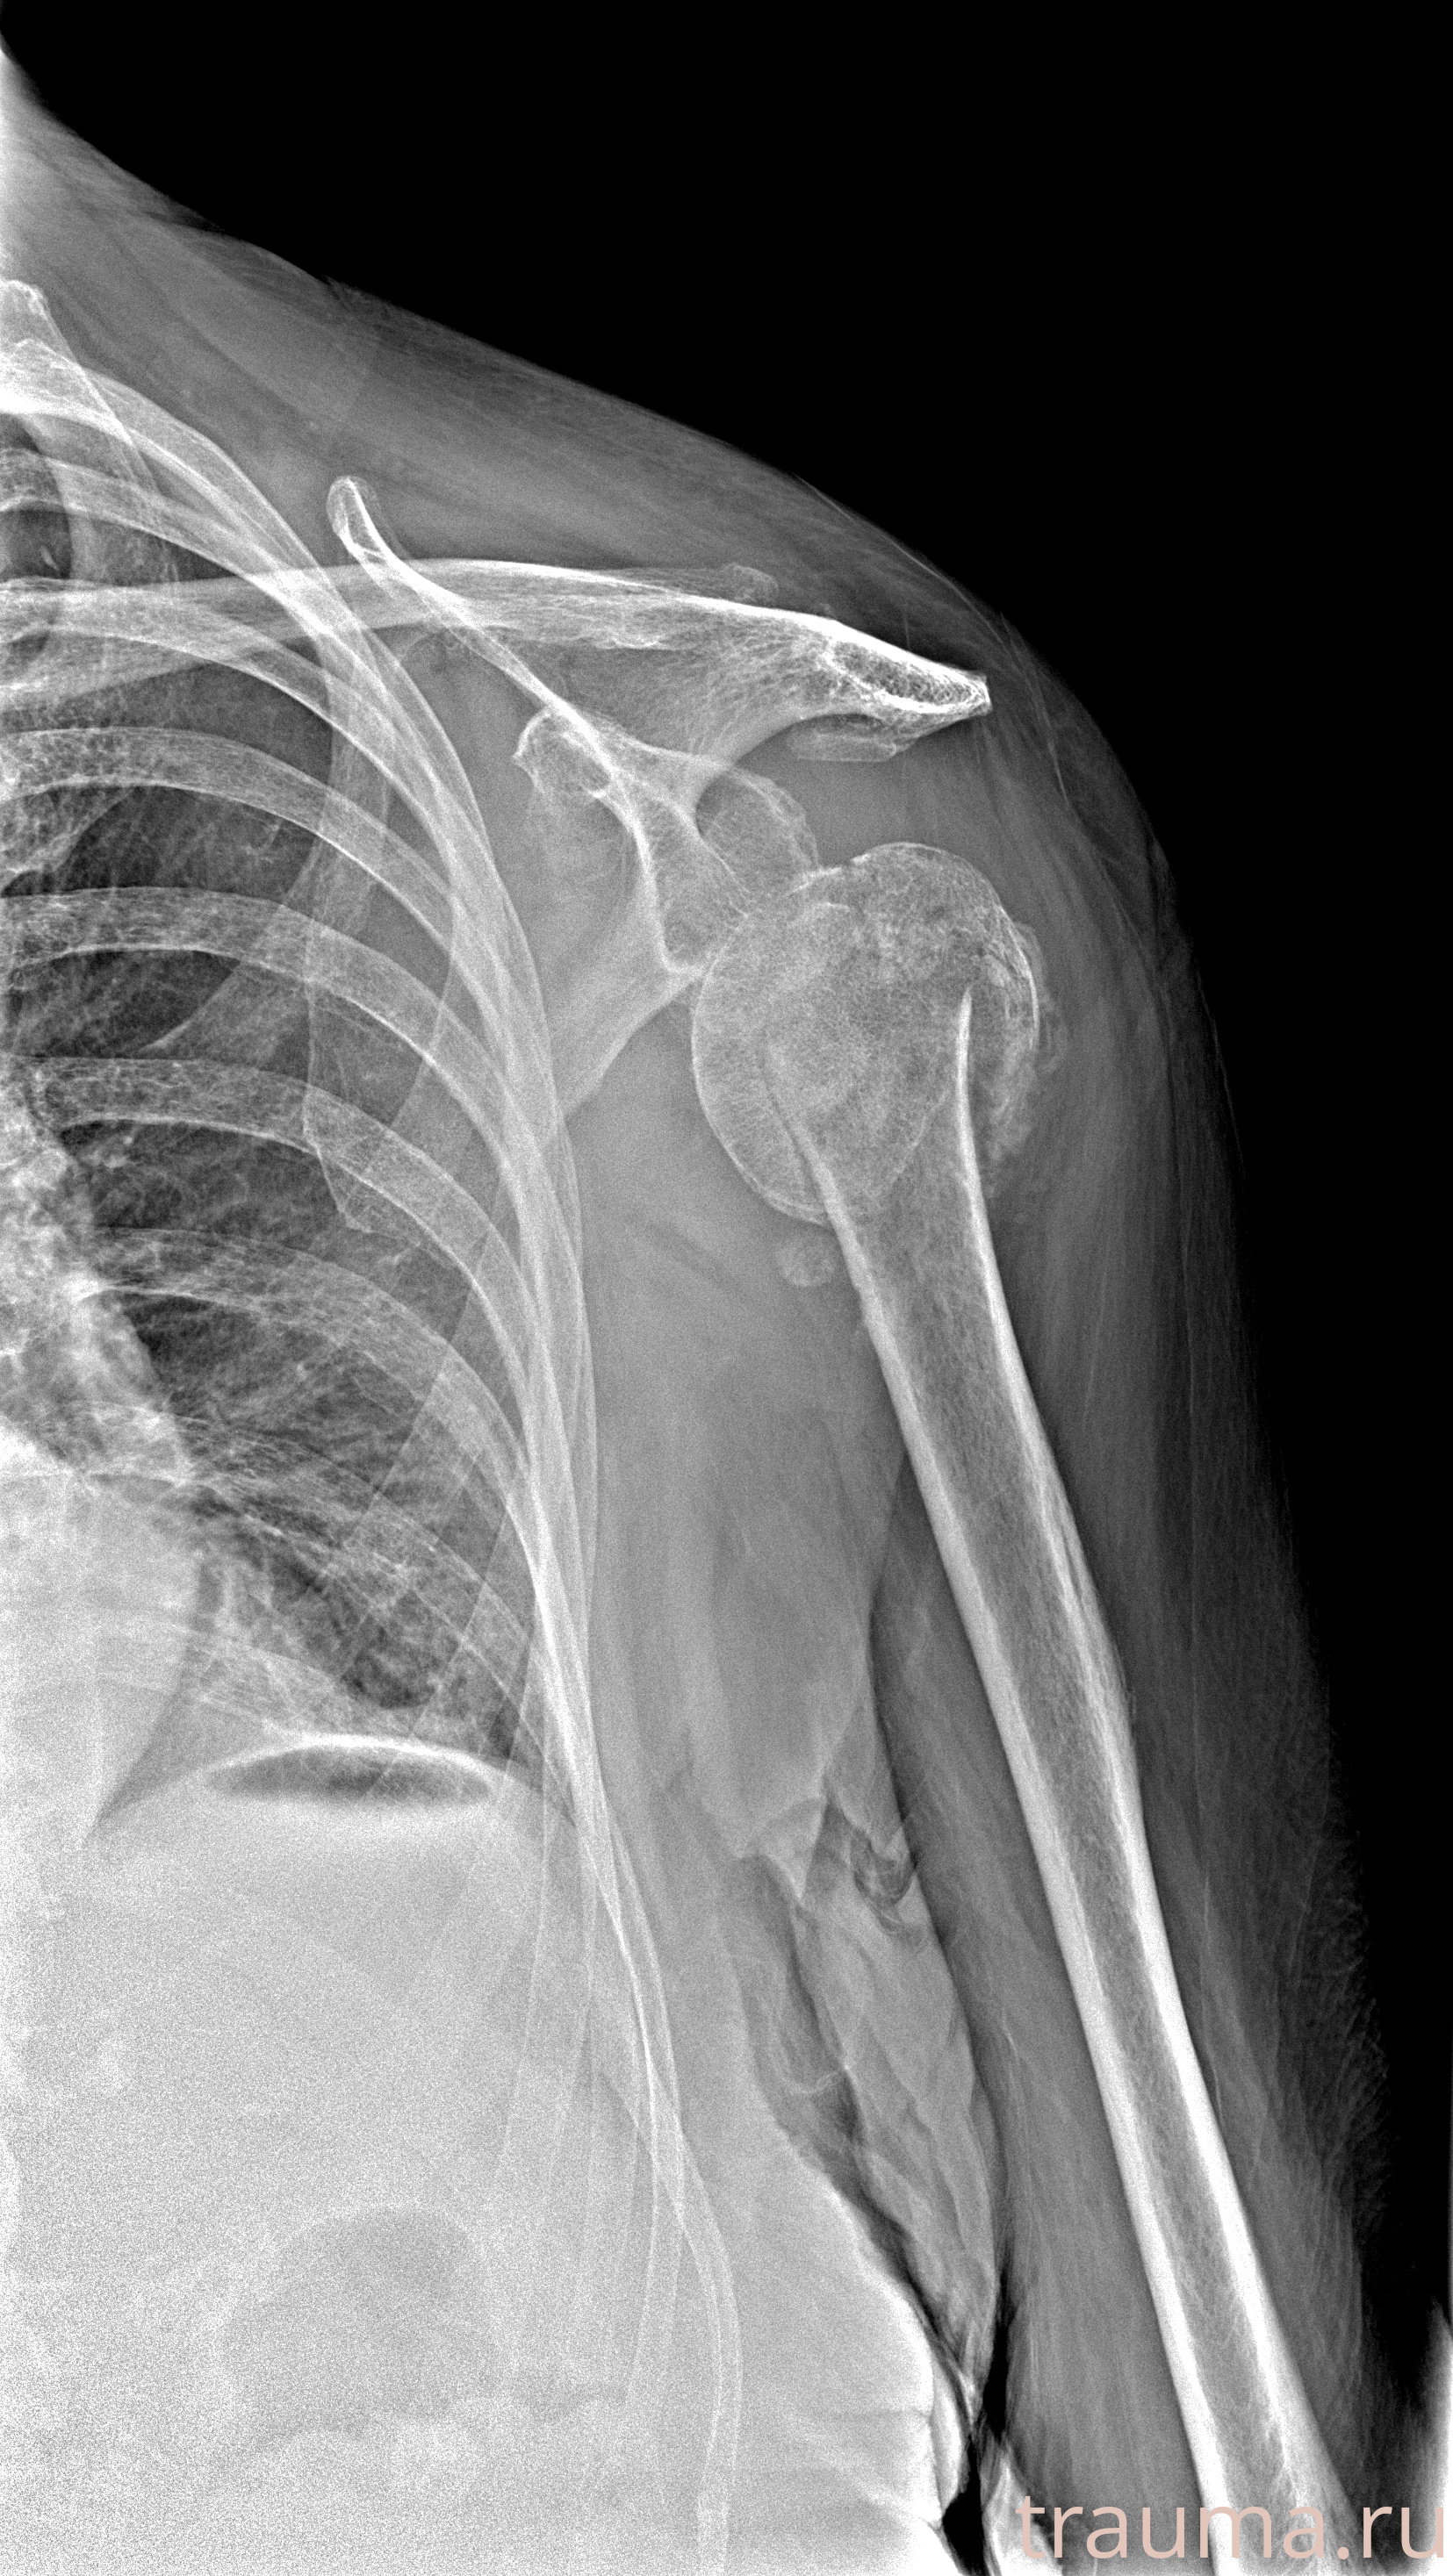

Рентгенограммы

Рентген на дому: по вашему адресу приезжает врач-рентгенолог, травматолог-ортопед с мобильным рентгеновским аппаратом, проводит диагностику травмы или заболевания, делает необходимые рентгенограммы, дает рекомендации по дальнейшему лечению. Получить качественные снимки в домашних условиях возможно благодаря уникальной методике, разработанной МосРентген Центром для института  Склифосовского